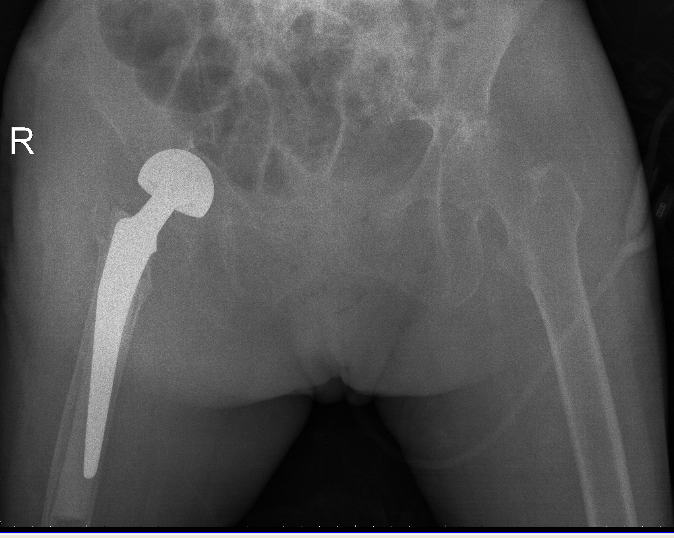

10月20日,老人家被送進了手術室行左側人工股骨頭置換術。吳主任根據方案按部就班地實施手術,娴熟地完成每一個手術步驟,精心地把控每一個細節,确保髋部良好的活動性和穩定性,以及雙下肢等長。整個手術過程非常流暢、一氣呵成。術中患者各項生命體征平穩,術後平安返回病房。

△右側(R)是賴婆婆3年前跌斷股骨術後,左側是本次手術術後。

△術後